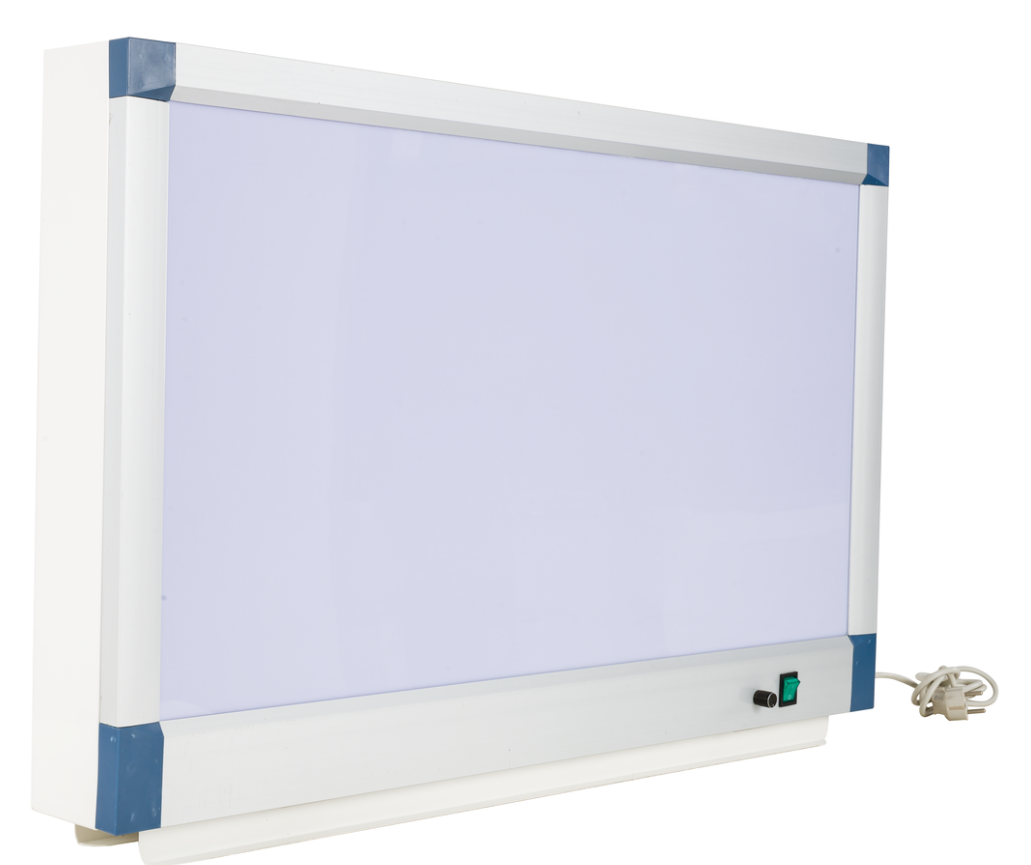

You are finding a singe LED X-ray film viewer with CE/ISO/FDA?

1.using imported energy-saving fluorescent tubes, long life time, high screen brightness, making the medical image details fully displayed, improving the diagnostic accuracy of reading film.

2.brightness can be adjusted continuously, is suitable for observing

all kinds of density X-ray film and CT film. the screen brightness is uniform, density difference is less than 20%.

3.special used aluminium alloy frame, ultra thin design(10cm), the surface is epoxy powder coated steel, long lasting as new, beautiful and luxurious.

4.using our company patent clip device"steel ball type clamp", inserting and taking out are convenient and flexible.

5.the front screen can be opened, making the fluorescent tubes change easier and more convenient.

| Material: | Alluminium |

| working voltage: | AC220V |

| power: | 48W 50HZ |

| light source: | LED |

| Frame size: | 440*585*110mm |

| Screen size: | 360*435mm |